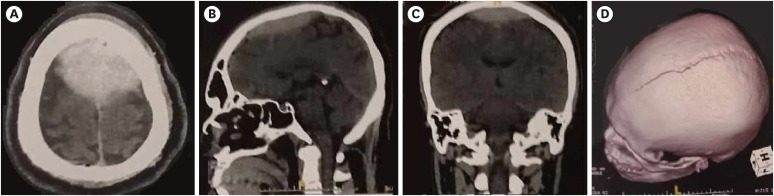

Vertex epidural hematomas are very uncommon complications of traumatic head injury. Besides the volume of the epidural bleeding, compression of the superior sagittal sinus may be source for added elevated intracranial pressure. Clinical presentation of such lesions is heterogenous and symptoms can develop in an acute to a chronic frame. Radiological diagnosis can sometimes be challenging. Due to its rarity, such lesions have been only reported on case reports and small series and the management remain controversial. Hereby we report 3 cases of surgically managed post traumatic acute epidural hematomas of the vertex. Wen also went through a literature-based discussion of clinical, radiological and therapeutic features related to this condition.

Abstract Image